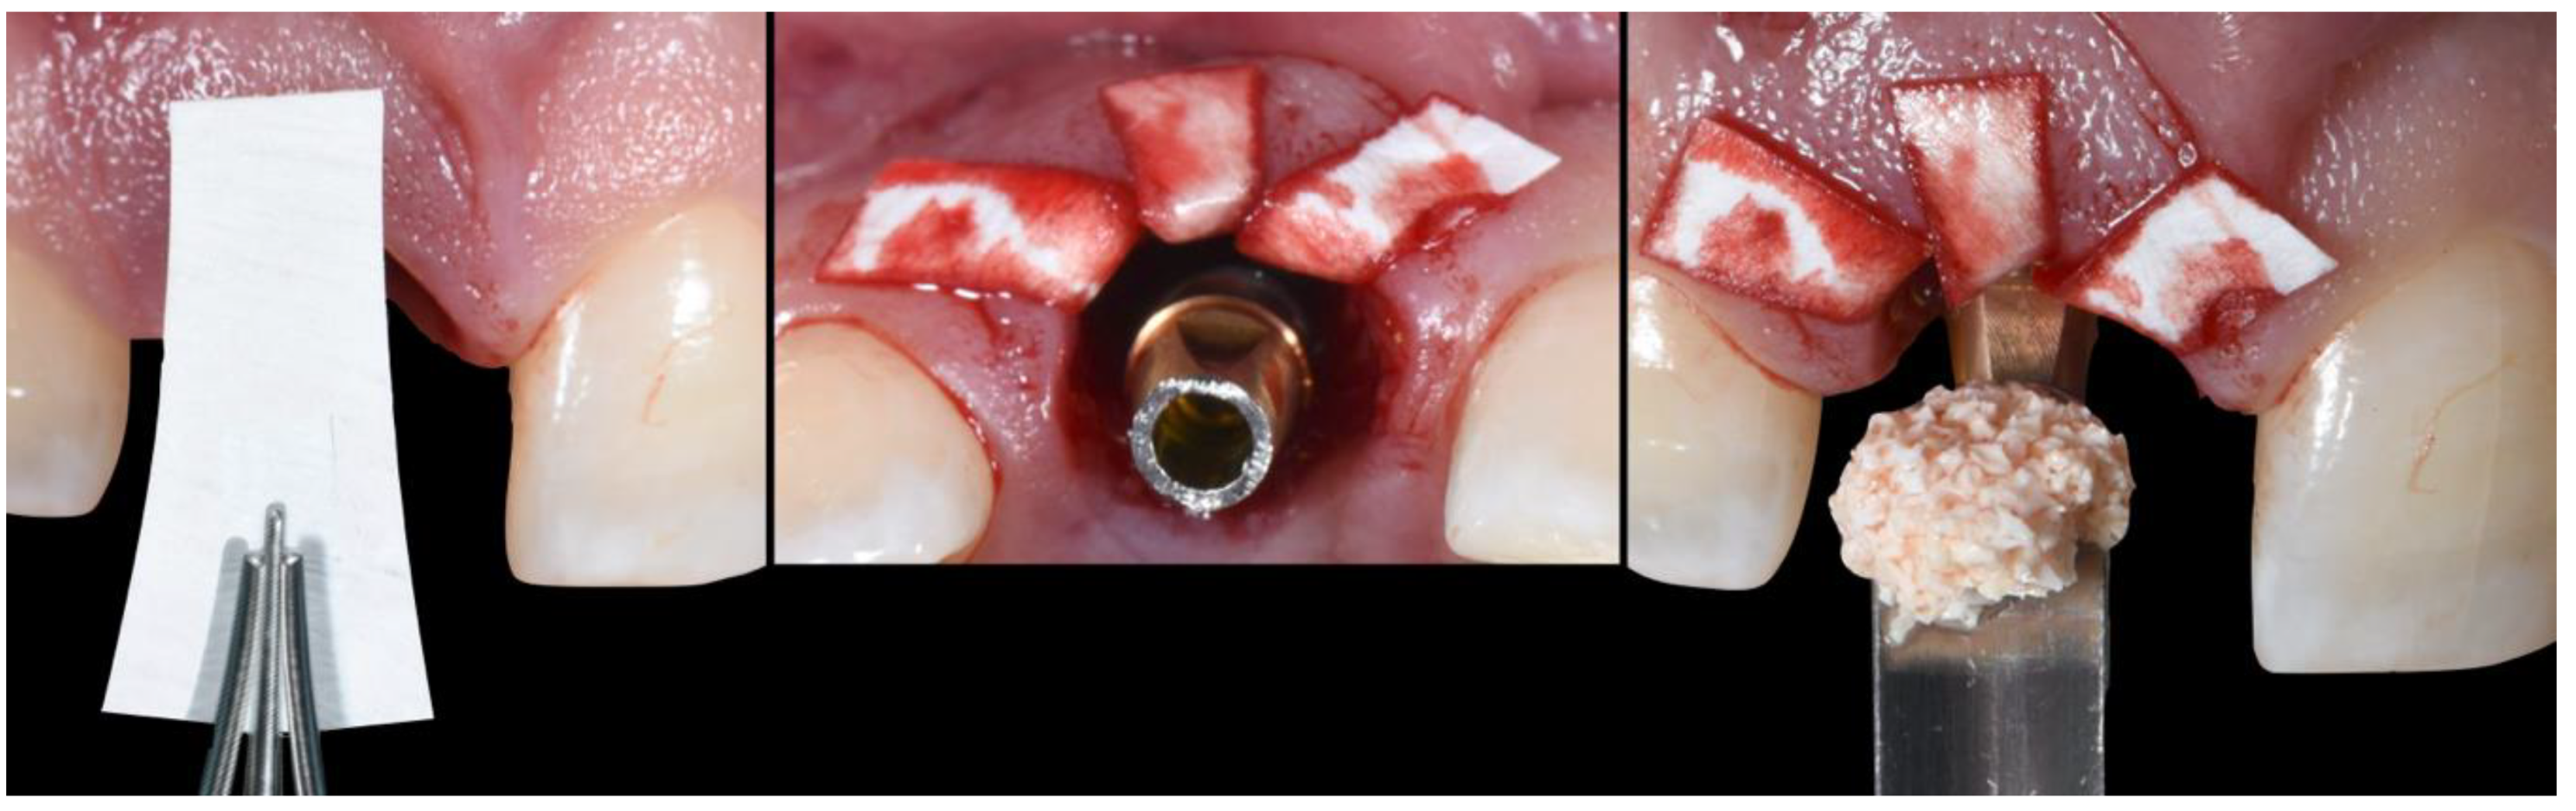

- (E)

- Bone replacement graft BRG introduction into the available space present within the socket, occupying both the soft and hard tissue zones present below the abutment’s shoulder.

- (F)

- Membrane adaptation and suturing with vertical mattress sutures.

- (G)

- Temporary prosthesis delivery, where the cervical margin is located supra-gingivally and comprises a 90′ emergence angle in relation to the abutment.

- (A)

- Supra-periosteal pouch design, demonstrating proper lateral and vertical extensions. The red lines demonstrate the pouch, while the yellow line demonstrates the mucogingival junction.

- (B)

- First abutment in place and membrane adaptation prior to BRG introduction.

- (C)

- Final relationship between first temporary prosthesis, abutment, and cervical gingival tissue.